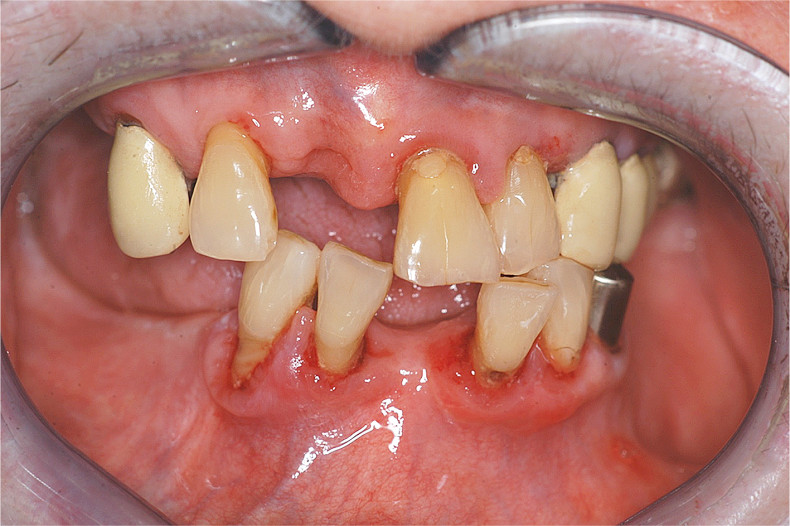

Entzündliche Parodontalerkrankungen

Ältere Patienten weisen einen höheren Anteil an fortgeschrittenen parodontalen Destruktionen auf als jüngere.1 Neben dauerhaften Entzündungen der Gingiva aufgrund einer mangelhaften Zahnpflege kann bei ihnen der Diabetes ein weiterer Risikofaktor für marginale Parodontitiden und damit für einen Zahnverlust sein. Die Parodontitis tritt bei Diabetikern häufiger in einer fortgeschritteneren Form und in Verbindung mit ausgeprägten Gingivitiden auf.15,21

Therapie von Parodontalerkrankungen

Die Behandlung marginaler Parodontopathien bei Menschen mit eingeschränkter Funktionalität und/oder systemischen Erkrankungen ist meistens problematisch. In vielen Fällen bleibt sie beschränkt auf eine schonende, aber gründliche Entfernung der supra- und subgingivalen harten und weichen Ablagerungen mit dem Ziel, den Verlauf der entzündlichen Prozesse aufzuhalten oder zumindest bis zu einem bestimmten Ausmaß unter Kontrolle halten zu können. Welche Behandlungen bei Patienten mit Allgemeinerkrankungen im Einzelnen durchgeführt werden sollten und können, ist abhängig vom oralen und allgemeinmedizinischen Erkrankungszustand sowie der Kooperationsfähigkeit des Patienten.